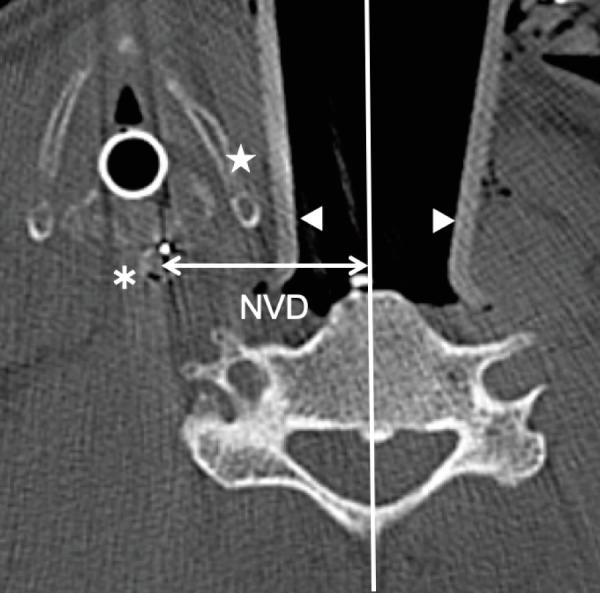

Sixteen patients who underwent anterior cervical spine surgery with intraoperative CT for registration of a navigation system without release of blade retraction were included. To investigate the status of the retracted esophagus and pharynx, the distance between the nasogastric tube and center of the vertebra (NVD) was measured at each disc and vertebral level (C4-7) using axial CT. The location of the cricoid cartilage, which may affect the shift of the esophagus and pharynx, was noted. Presence or absence of contact between the esophagus and the edge of the surgical blade was investigated.

The NVDs were 28.0, 28.3, 28.9, 27.2, 24.7, 19.9, and 13.8 mm at C4, C4/5, C5, C5/6, C6, C6/7, and C7, respectively; NVDs at C6/7 or more caudal levels were significantly shorter than those at C6 or more cranial levels (P < 0.001). The cricoid cartilage was observed at the C4-C5/6 level. Esophageal contact with the edge of the blade was observed in nine cases at C6 or more caudal levels.